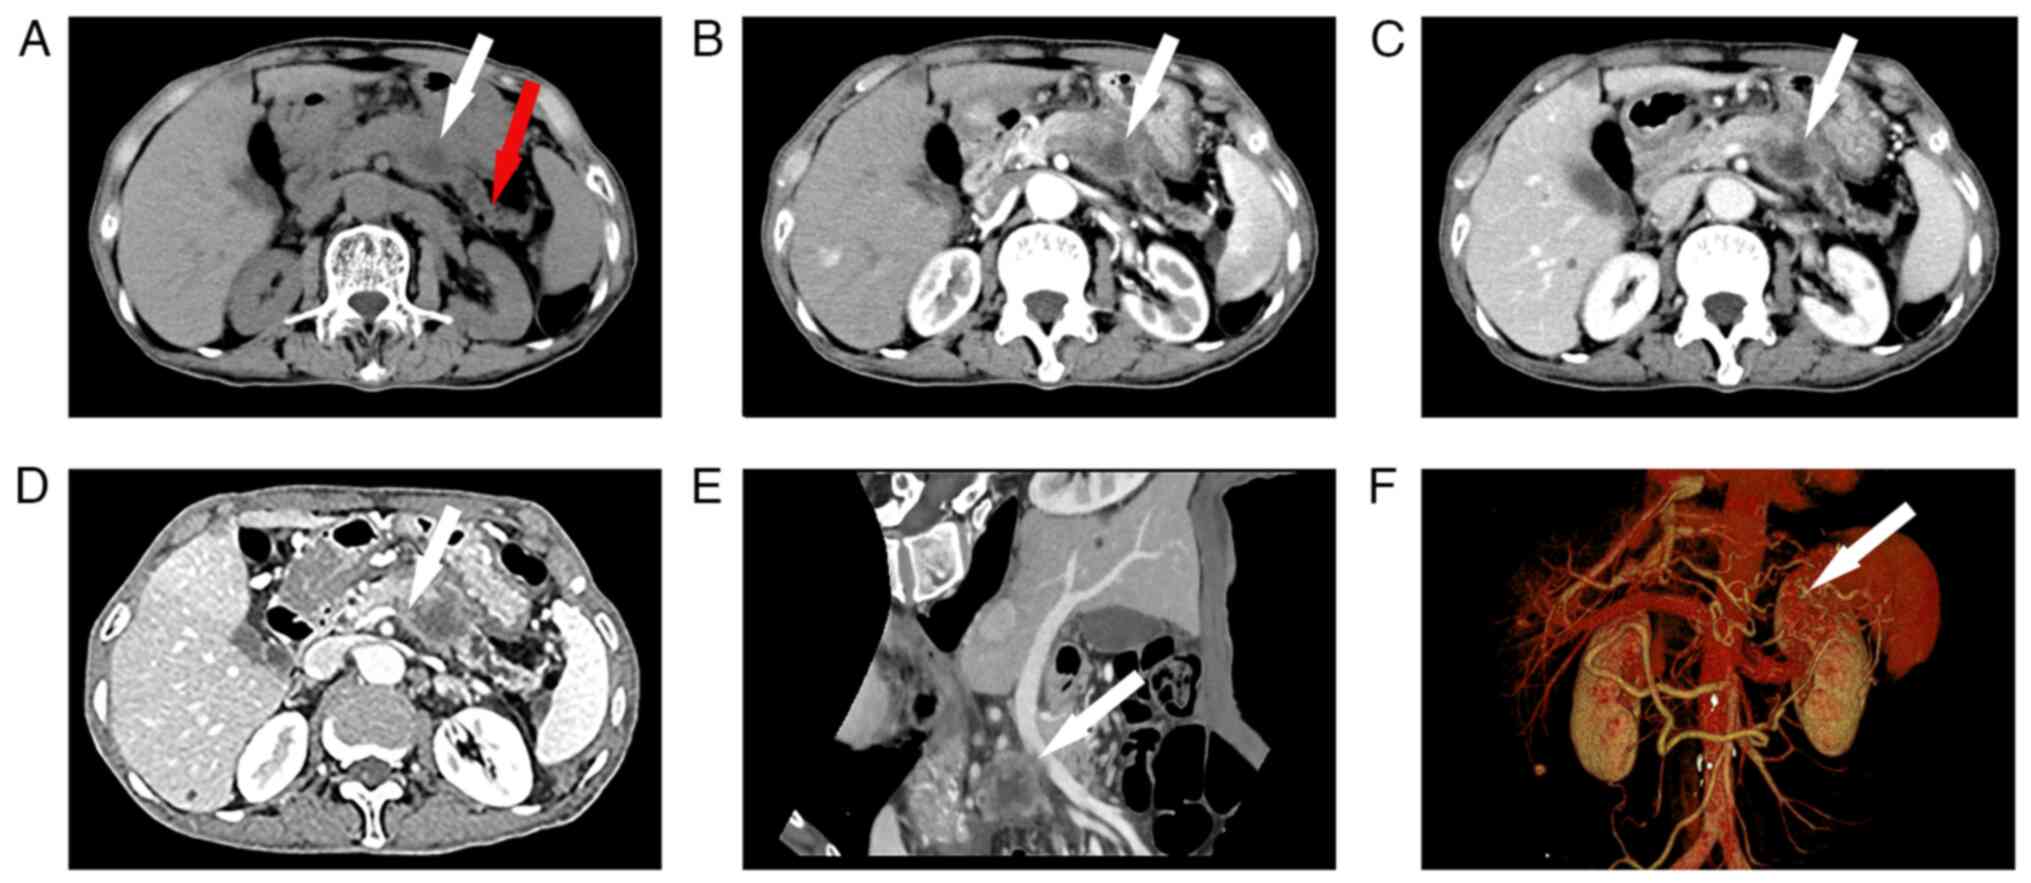

A 78-year-old male patient presented to our hospital with chronic intermittent pain in the left upper abdomen for one year and progressive aggravation for one month. The patient had been diagnosed with pancreatitis at a local hospital 1 year ago, and the pain symptoms were relieved after medical treatment. One month prior, he presented with marked left upper abdominal pain that increased while standing upright or walking. The patient had no history of trauma, high blood pressure, or diabetes, nor did he have a family history of pancreatic cancer. Physical examination revealed that his heart rate, body temperature and blood pressure were 87 bpm, 36.2°C, and 140/80 mmHg, respectively. The abdomen was soft and had left upper abdominal tenderness without abdominal muscle tension or rebound tenderness. Laboratory tests showed the following levels (reference range for normal): carbohydrate antigen 199 (CA199), serum amylase, and serum potassium levels were 1968 U/ml (0–37 U/ml), 332 U/L (35–135 U/L), and 3.1 mmol/l (3.5–5.5 mmol/l), respectively. Abdominal computed tomography (CT) revealed an irregular mass located in the pancreatic body and tail with no clear boundary, pancreatic body and tail atrophy, and the pancreatic duct dilation significantly. CT enhancement scan showed a central region with non-enhancement low-density but enhancement of the surrounding region of the tumor (Fig. 1A-C). On CT angiography, the structure of the splenic vein was not clearly displayed, and portal vein stenosis with portal hypertension (Fig. 1D-F). 18F-FDG (F-18-deoxyglucose) positron emission tomography (PET)/CT revealed a semisolid (cystic with solid fractions) mass measuring 4.5×3.5 cm on CT images with a maximum standardized uptake value of 7.9 in the pancreatic body (Fig. 2). Endoscopic ultrasonography (EUS) showed that the posterior wall of the upper portion of the gastric body was raised from the surface of the pancreas, revealing gastric varices (Fig. 3A). Ultrasonography showed an ill-defined hypoechoic mass lesion in the pancreatic body measuring 4.5×3.5 cm (Fig. 3B). Endoscopic ultrasound-guided tissue sampling for histological examination confirmed the presence of highly pleomorphic neoplastic cells and non-neoplastic osteoclast-like giant cells. Immunohistochemical staining revealed CD68 reactivity in OGCs, and the Ki-67 labeling index was 15% (Fig. 3C and D). Unfortunately, at the time of diagnosis, the patient's disease had advanced beyond the time of surgical intervention. According to the guidelines of the Chinese Society of Clinical Oncology, patients were treated with the following chemotherapy regimen: gemcitabine was administered on the first day and eighth day as an intravenous infusion over 30 min at a dose of 1200 mg, and tegafur, gimeracil, and oteracil potassium capsules were administered continuously at a dose of 80 mg/day orally for 14 consecutive days (3 weeks for a treatment course). Unfortunately, despite receiving chemotherapy, the patient showed a poor response to systemic chemotherapy because his condition quickly worsened, and he died 6 months after hospital discharge.

Figure 1.

(A) On the plain CT scan, a large mass with heterogeneous density and indistinct borders located in the pancreatic body (white arrow), and ductal dilatation of the main pancreatic duct (red arrow) were observed. Contrast-enhanced axial CT images showed the mass (white arrow) with heterogeneous enhancement in the (B) arterial and (C) venous phase. (D) CT angiography revealed the presence of obvious portal vein stenosis with portal hypertension (white arrow). (E) CT-multiplanar reconstruction of the portal vein indicated stenosis of the vascular lumen (white arrow). (F) Three-dimensional reconstruction showed a large amount of collateral circulation around the spleen (white arrow). CT, computed tomography.